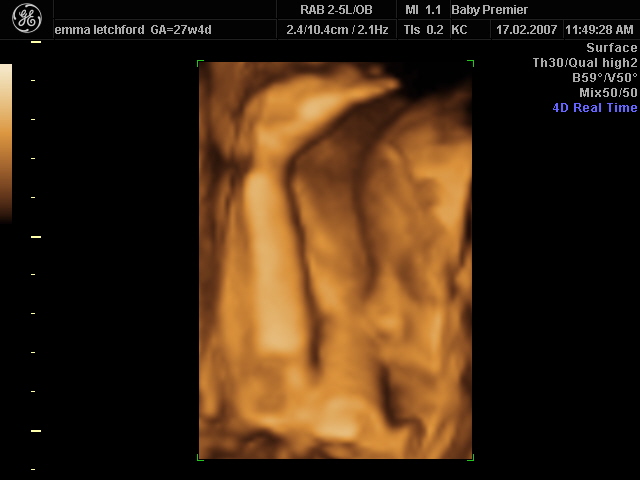

BABY LETCHFORD 3

BABY LETCHFORD_3.JPG